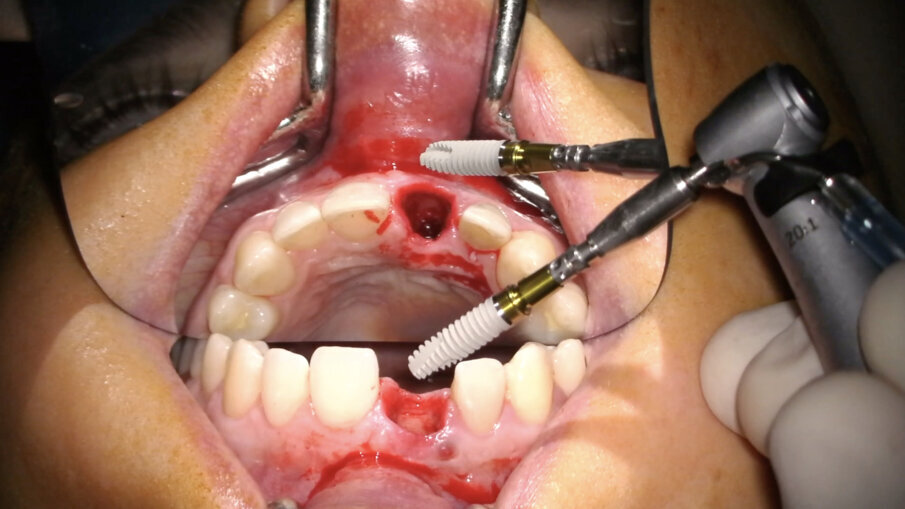

- Posizionamento implantare

L’impianto (XIVE – Dentsply Sirona) è stato posizionato centralmente con un’inclinazione palatale al fine di evitare che il foro di accesso della vite cadesse sul margine incisale del provvisorio o, ancor peggio, sulla sua superficie vestibolare. Il gap osseo vestibolare è stato riempito con Geistlich Bio-Oss (Geistlich Pharma) (Figg. 16-19).

Fig. 16_Inserimento dell’impianto Xive FX 3.8.

Fig. 17_Posizione corretta dell’impianto post-estrattivo.

Fig. 18_Posizionamento del biomateriale.

Fig. 19_Gestione del biomateriale.